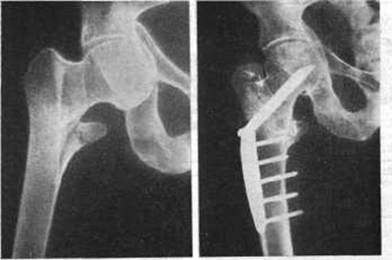

Поскольку возникновение ложного сустава после перелома чаще всего происходит во время сращения костей, диагностика проводится на основании рентгенологического исследования. Это включает в себя снятие фиксирующей повязки с пациента и рентген. Жалобы пациента учитываются, но не являются решающими для постановки диагноза.

Рентгенограммы — это диагностический инструмент в случае образования ложного сустава после перелома.

В процессе изучения рентгеновского снимка, врач обращает внимание на такие признаки патологии:

- Наличие несвязанных переломов;

- Обтачивание концов шрапнели и раненых костей до округлости и гладкости;

- Наличие на месте травмы медицинских ретенционных пластин, частично или полностью перекрывающих приток крови и кислорода к пораженным органам и частям тела;

- Наличие ярко выраженного разрыва на стыке двух отломков.

Лечение основано на использовании специальных пластин и фиксирующих винтов для фиксации сломанных костей. Этот метод используется для обеспечения правильного сращения костей после переломов плеча, бедра и других частей тела.

Устойчивый остеосинтез

Чтобы установить пластину, хирург должен полностью обнажить кость в месте перелома. Эта процедура проводится под общим наркозом.

Этот вид манипуляции применяется для лечения ложного сустава, образовавшегося после перелома бедра, и других костных фрагментов с сильно раздробленными костями или большими промежутками между отломками.